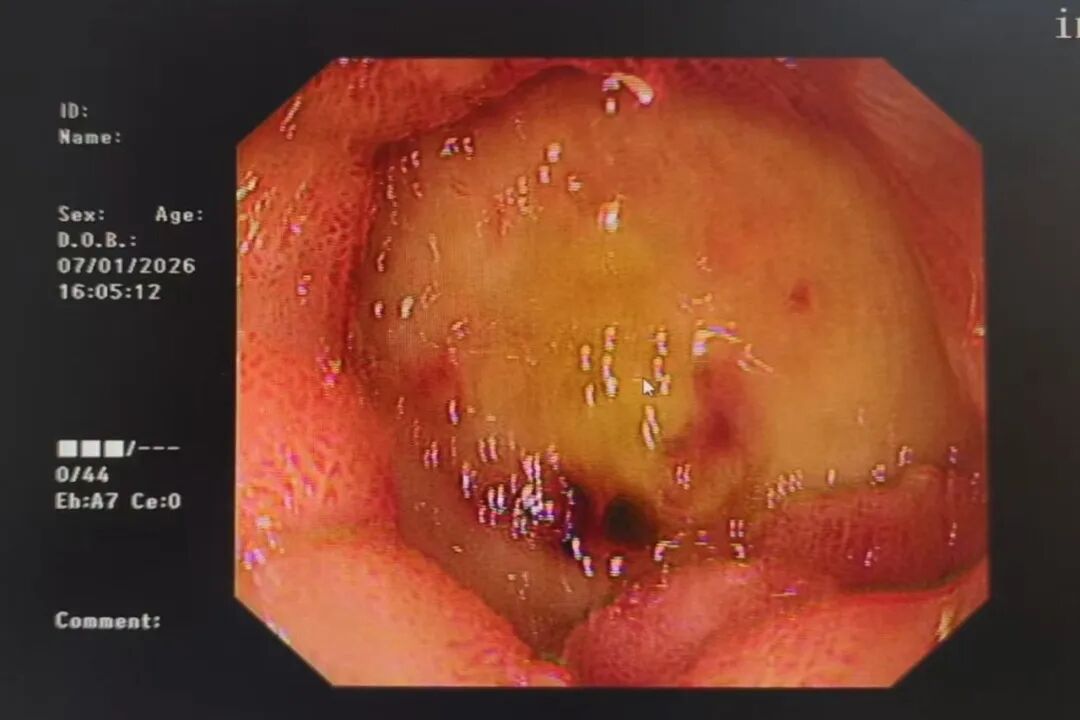

据悉,该患者为男性,58岁,既往有鼻咽癌并肝、肺、骨、左颈部淋巴结多发转移病史,此次因“右上腹疼痛8小时”入住消化内科。入院查体显示,患者急性面容,表情痛苦,腹部膨隆,上腹部腹肌稍紧张,全腹部压痛、反跳痛,肝区有叩击痛,肠鸣音正常。入院后完善相关检查,影像结果提示存在转移瘤可能,需进一步检查明确病因。在住院期间,患者突然黑便,血压急剧下降,脸色白得像纸,整个人陷入休克边缘,生命体征极不稳定。他的血红蛋白仅剩32g/L(正常成年男性为120-160g/L),相当于全身血液濒临“流干”!这对于肝癌并多发转移、身体状况本就十分脆弱的患者而言,生命已悬于一线。危急关头,消化内科团队立即行急诊胃镜检查,发现十二指肠巨大溃疡并出血。内镜医生凭借精准识别与敏锐判断,考虑是动脉出血,未行常规的内镜下止血处理,而是通过完善增强CT检查,确认是十二指肠上动脉假性动脉瘤破裂,这就像体内有一颗随时会爆炸的“小炸弹”。

面对如此凶险复杂的病情,消化内科团队迅速启动应急预案。排除相关禁忌症后,介入团队立即为患者行选择性动脉造影术+胃十二指肠动脉栓塞术。通过微导管精确找到了出血的动脉——那个破裂的“小炸弹”。凭借一根细如发丝的导丝、一次精准的栓塞操作,成功为患者止住了大出血。这场紧急抢救的微创手术,没有开刀,没有大创口,仅通过患者大腿根部一个针眼大小的穿刺点,便完成了高难度的血管“拆弹”,把患者从死亡线上拉了回来。